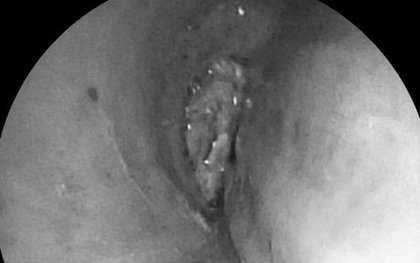

Người phụ nữ 57 tuổi bị tức ngực, bác sĩ gắp ra thứ "đáng sợ" bên trong

Các bác sĩ Khoa Nội Hô hấp, Bệnh viện Bãi Cháy vừa nội soi phế quản thành công gắp dị vật nằm sâu trong phế quản của một nữ bệnh nhân 57 tuổi.